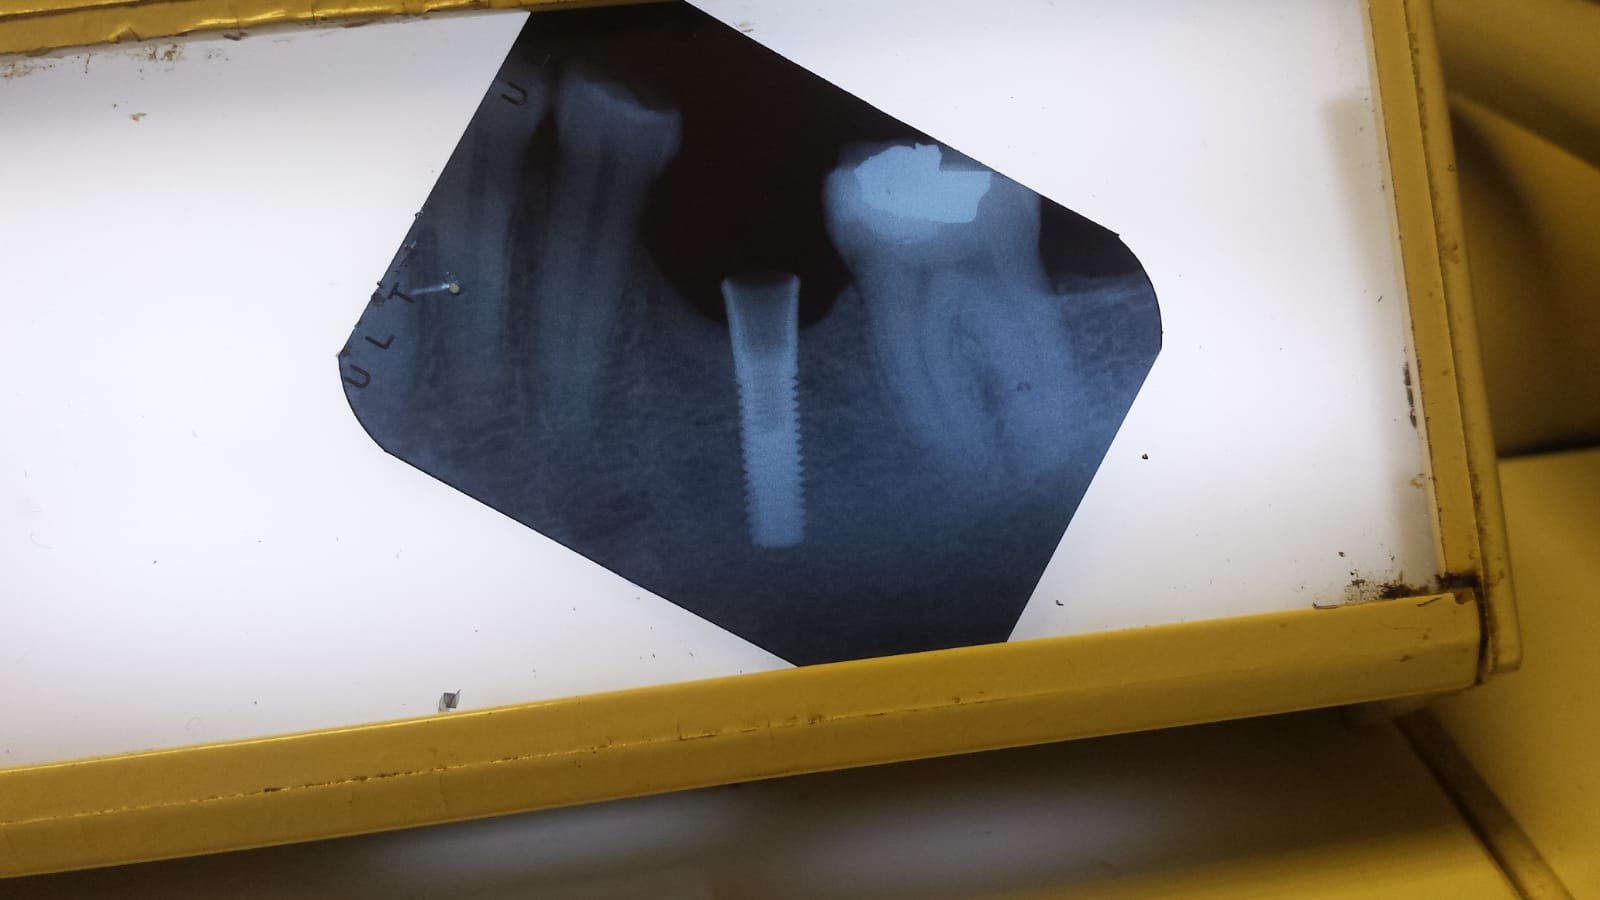

¿Qué implante es?

Necesito averiguar el tipo de implante de la siguiente radiografía.

No se que implante es.

aporto imagenes un abrtazo.gracias.